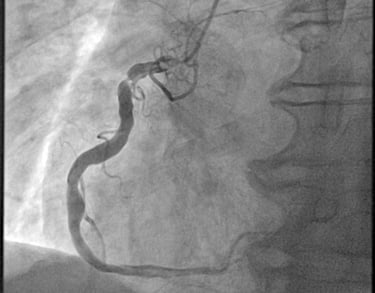

CORONAROGRAFIA

La Coronarografia è l’esame piu’ approfondito per valutare la presenza di restringimenti (“stenosi”) a carico delle arterie coronarie, ovvero delle arterie che nutrono il cuore. Viene effettuata tramite utilizzo di appositi cateteri che vengono inseriti attraverso l'arteria radiale o femorale. Per acquisire le immagini viene utilizzato un liquido chiamato “mezzo di contrasto” che opacizza il lume delle arterie mescolandosi al sangue. Le immagini vengono acquisite da un macchinario che emette una debole radiazione e registra le immagini.

ANGIOPLASTICA

Angioplastica coronarica e lo stent

Si tratta del piu' comune trattamento attualmente utilizzato per curare l'aterosclerosi coronarica. E' una metodica che si avvale di molteplici strumenti appositamente ideati e realizzati e puo' essere effettuata subito dopo la coronarografia, utilizzando la stessa via di accesso arterioso. Solitamente, il paziente sottoposto ad angioplastica coronarica programmata puo' essere dimesso il giorno successivo alla procedura. Lo stent coronarico e' un dispositivo di grandezza millimetrica, in lega metallica biocompatibile (quindi senza fenomeni di rigetto), che viene utilizzato di solito dopo la dilatazione dell'arteria coronarica con il palloncino, per mantenere la pervietà della arteria.